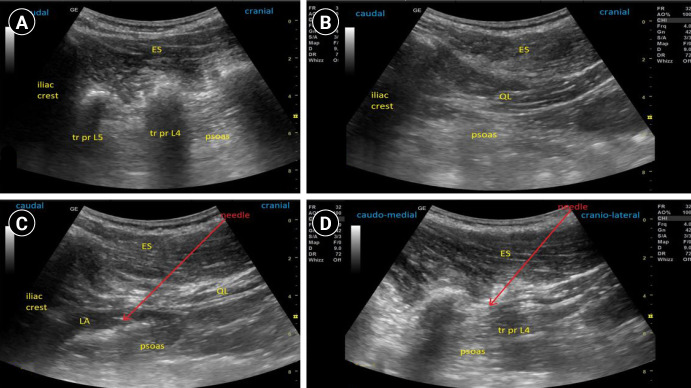

Background: Acetabular fracture surgery can cause severe postoperative pain. A combined lumbar erector spinae plane block and paraspinous sagittal shift quadratus lumborum block may augment analgesia.

Methods: Fifty two patients undergoing posterior column acetabular surgery were divided into: Group Single puncture combined lumbar Erector spinae and Quadratus lumborum block (SEQ), patients who received SEQ block before anesthesia; and Group morphine (MOR), those who received general anesthesia (GA) and morphine.